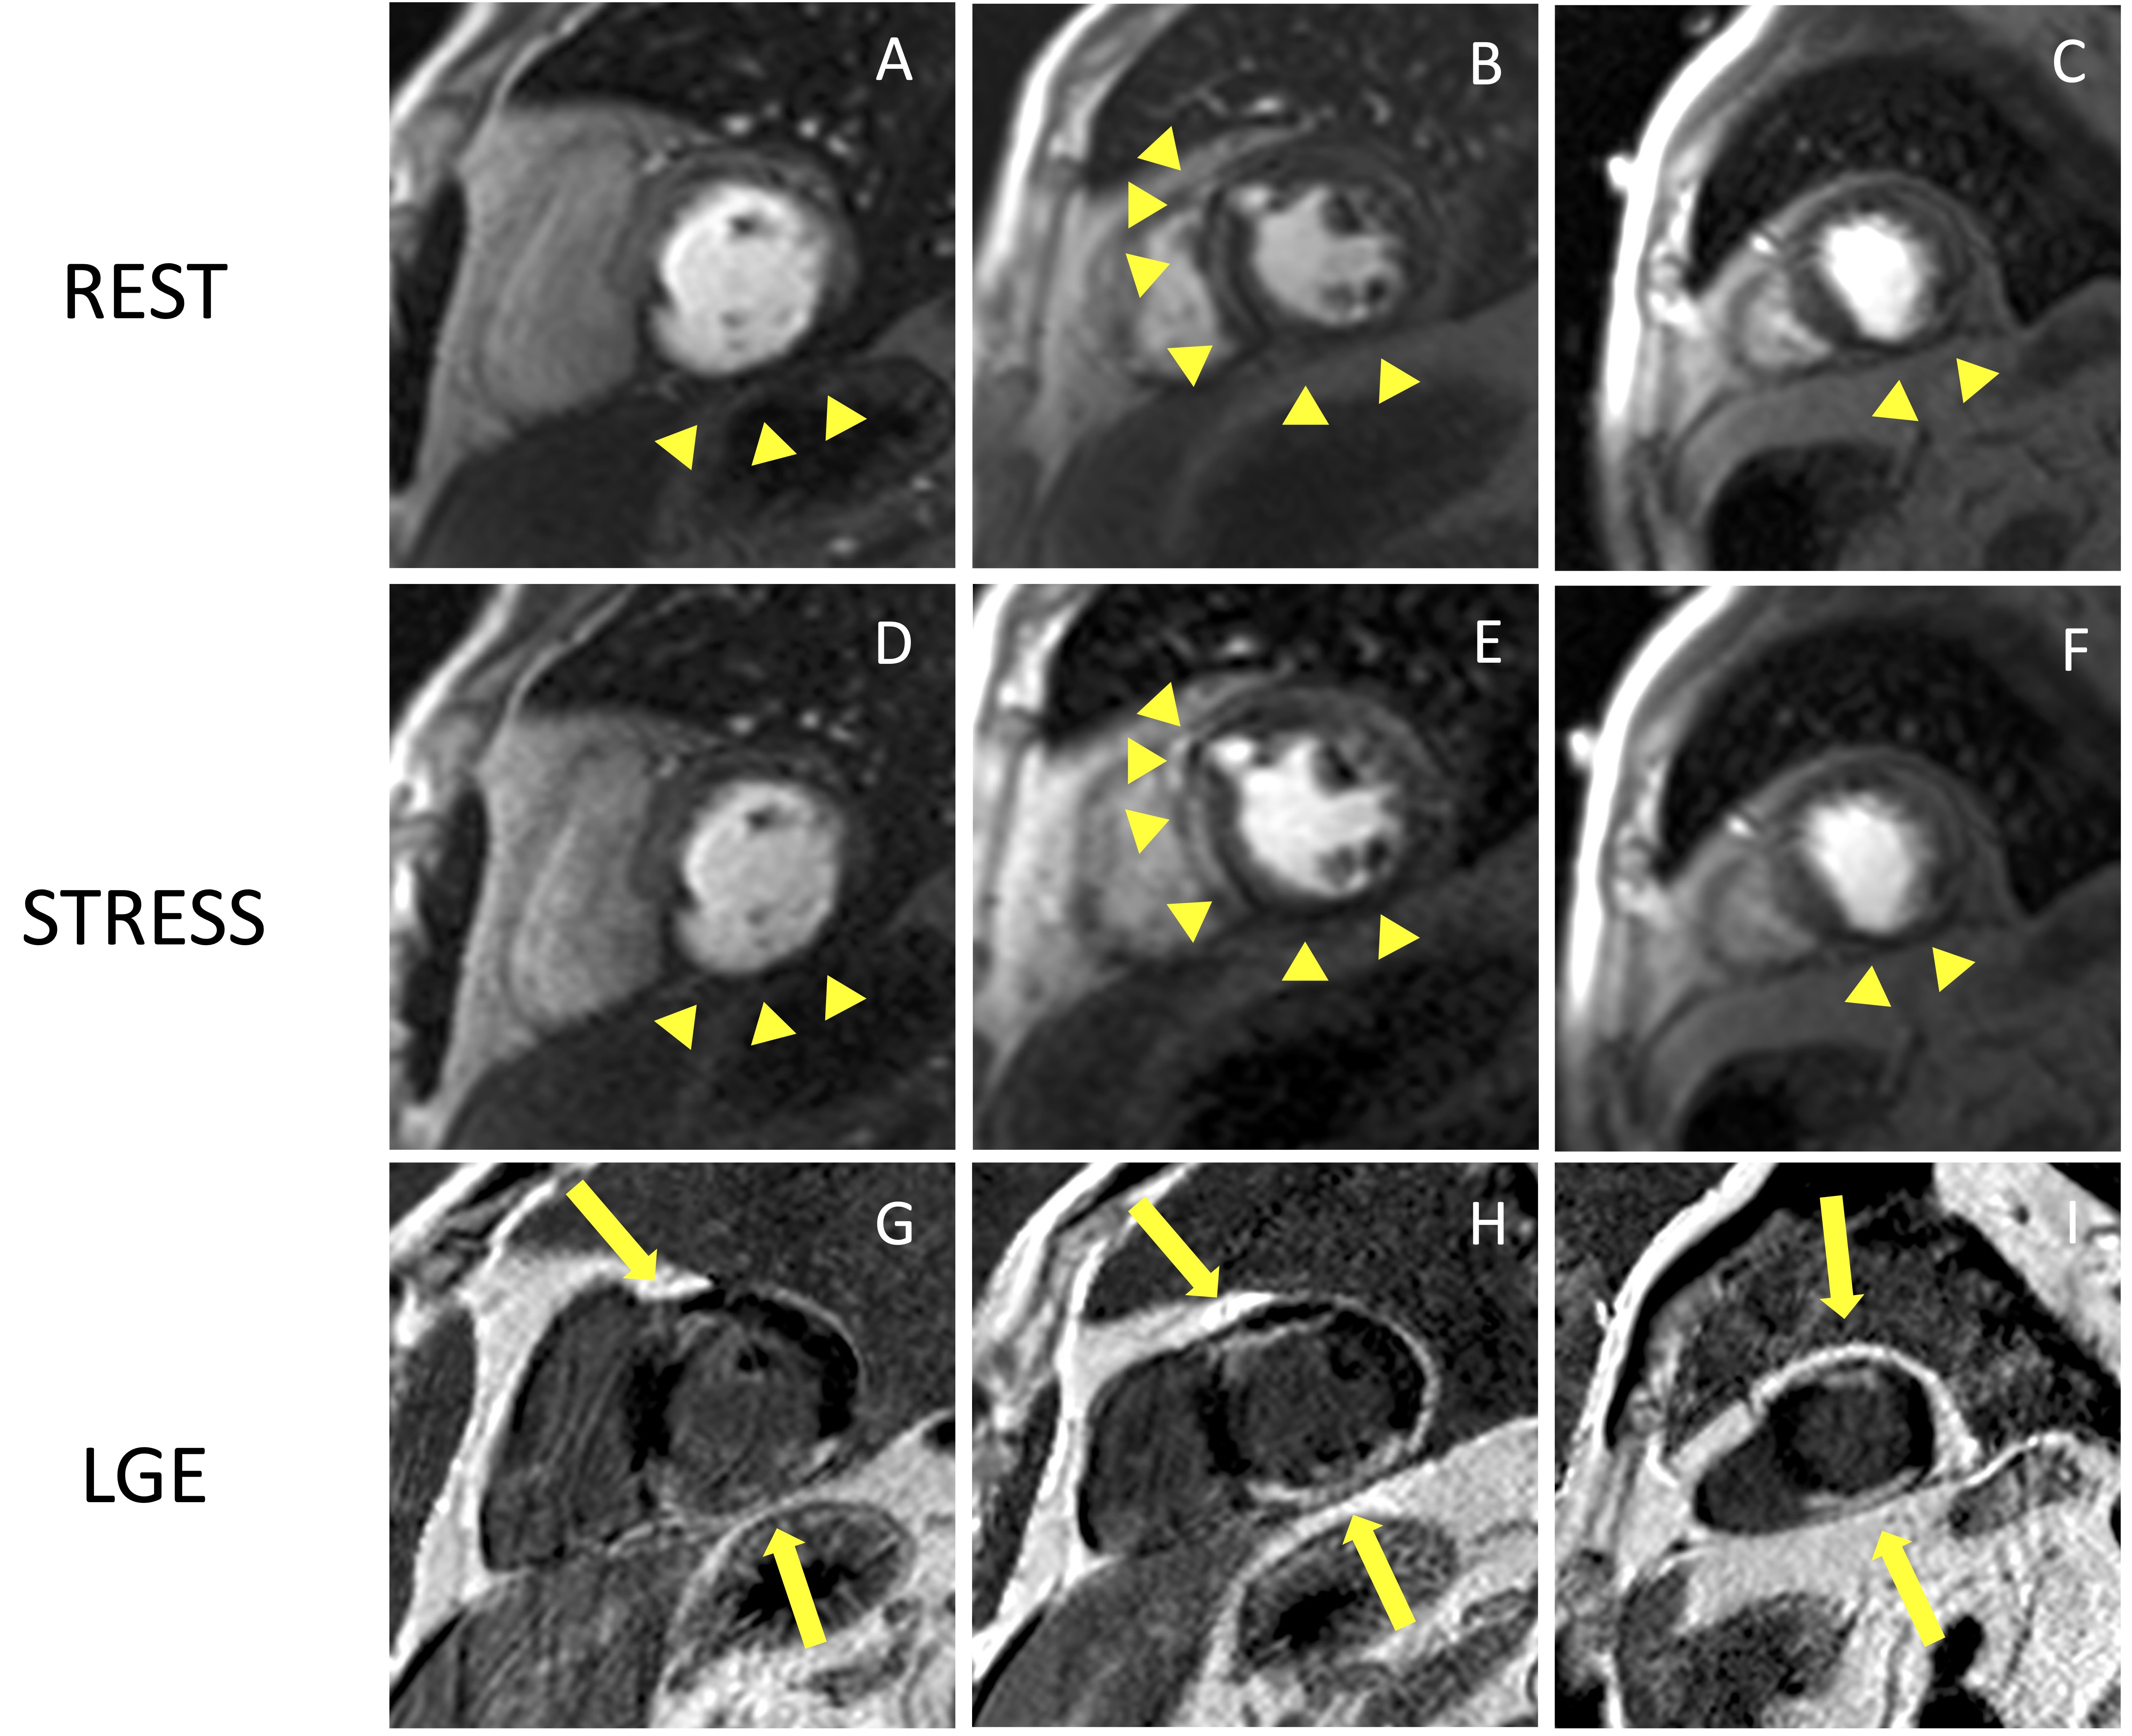

Fig. 5.Example of CMR adenosine-stress perfusion in the presence of

ischemic scar. This is the case of a 68-year-old man with a history of subacute

myocardial infarction and previous unsuccessful percutaneous angioplasty on the

RCA. Short axis rest and stress perfusion images are shown respectively at the

basal (A,D), mid-ventricular (B,E), and apical (C,F) level. There is

evidence of hypoperfusion, appearing as a hypointense subendocardial area in the

inferior septum, inferior wall and in the mid portion of the anterior wall

(yellow arrow heads). Corresponding LGE images (G,H,I) show ischemic scars

(yellow arrow lines) with a transmural distribution in the inferior septum and

inferior wall. Moreover, there is subendocardial LGE with a 50–75%

transmurality in the anterior wall. The perfusion defects appear both in the rest

and stress images and are related to the presence of non-viable myocardium (scar

transmurality